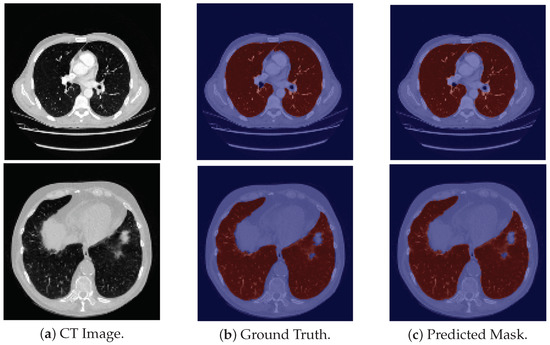

Concerning the VESSEL12 dataset, the model is able to produce good segmentation masks (see Figure 4), in general, for all ten scans, which were translated on a higher DSC, since this dataset does not contain intricate patterns. Moreover, the model does not erroneously classify other darker structures that are present in some slices as lungs.

Figure 4. Examples of VESSEL12 images for which the model produces good segmentation masks.

Applsci 12 01959 g004